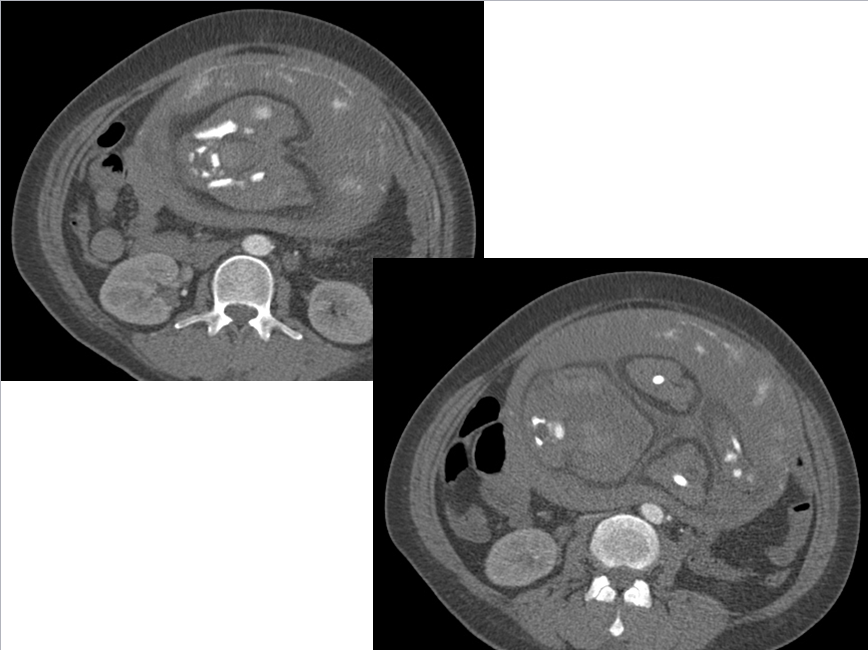

CT表现:自主动脉根部起至腹主动脉肾动脉水平可见撕裂之动脉内膜瓣影,子宫腔内可见胎儿影。

3、真、假腔的显示:真假腔可同时显影,或假腔强化和排空比真腔延迟;假腔内常有血栓形成可呈略高密度影,当多个破口存在时,真假腔较难区分。一般情况下假腔较大,真腔较小。

4、受累分支及范围:确认分支血管供血状况,观察主要器官的供血血管是发自真腔还是假腔。

显示冠状动脉、头臂动脉、腹腔内脏器动脉及髂动脉起源于真或假腔、是否受压推移。如果受夹层累及,可见内膜片线状充盈缺损影自血管开口处伸入分支血管腔内。